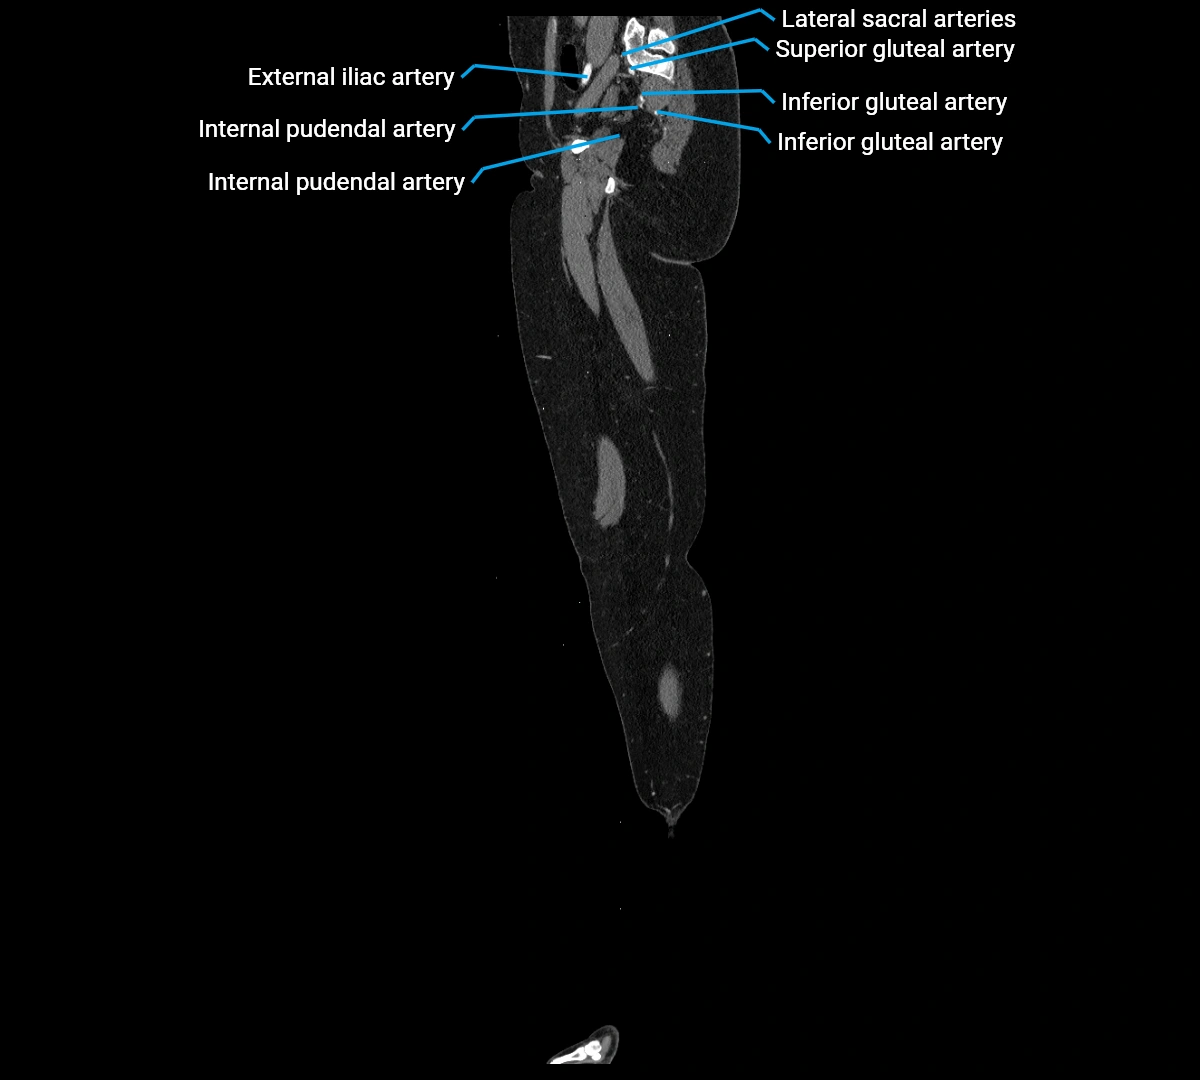

CT images

image

Contrast-enhanced CT (CTA):

• Gold standard for abdominal aortic imaging

• Provides excellent detail of lumen, wall, aneurysm, thrombus, and branch vessels

• Multiplanar and 3D reconstructions help in aneurysm measurement, stent graft planning, and dissection evaluation